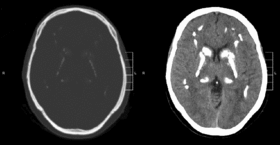

متلازمة فار أو تكلّس العقد القاعدية مجهول السبب هو مرض وراثي عصبي نادر[1] ذو وراثة سائدة يتميّز بترسّبات كلسية غير طبيعية في مناطق بالدماغ تتحكم بالحركة. عن طريق التصوير المقطعي المحوسب، يتم رؤية التكلس أساسًا في منطقة العقد القاعدية وفي مناطق أخرى مثل القشرة المخية.[2]